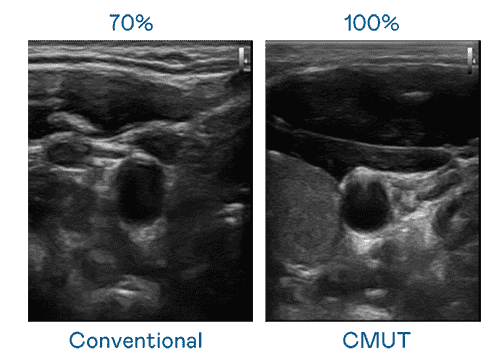

CMUT 技术是一种用电容式微机电元件来产生超音波讯号的技术。。。。与传统 PZT 压电式技术相比,,CMUT 频宽增加 30%,,,,更宽频的超音波讯号让影像解析度大幅提升,,,是实现高影像品质医疗超音波扫描、、、、促进精准医疗发展的关键技术。。。。

超音波影像的解析度高低,,,首先取决于探头能发出的讯号频宽。。。2121非凡 CMUT 可提供高清晰的超音波讯号,,提供高频宽、、、高灵敏度、、影像纹理细节更高的超音波影像,,协助医护人员缩短影像判读时间及利用精准的医疗影像进行诊断。。。。